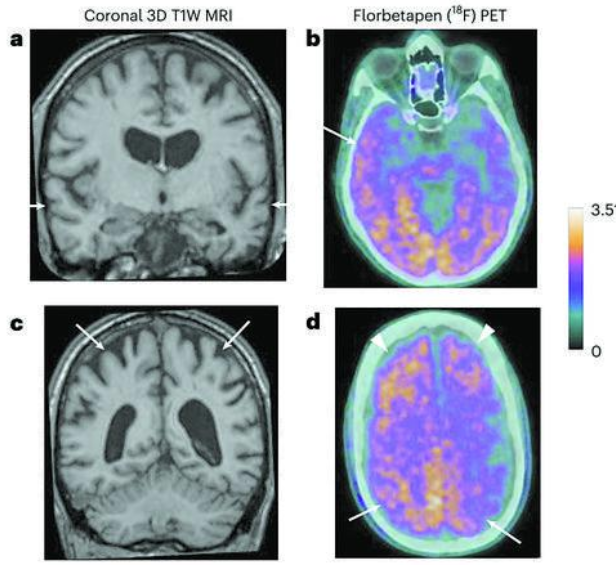

其中5人出現了與早發性癡呆(症狀出現於38—55歲)一致的症狀,符合阿爾茨海默病的診斷標準(在兩個或兩個以上認知領域出現進展性障礙,嚴重程度足以影響日常活動)。其餘3人中,一人出現了符合中度認知障礙診斷標準的症狀(開始於42歲),另一人僅有主觀認知症狀,第三人無症狀。

生物標志物分析在無症狀時不能用於診斷阿爾茨海默病,但可以支持兩名確診患者的診斷,並表明另一人已出現阿爾茨海默病的跡象。團隊還對兩名研究期間去世的人做了屍檢,包括大量腦組織取樣,其中一名患者也顯示出阿爾茨海默病的病理。